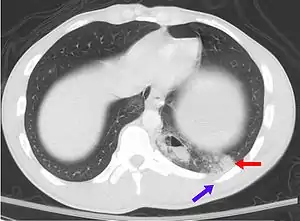

A CT scan showing a pulmonary contusion (red arrow) accompanied by a rib fracture (purple arrow)

Severe pulmonary contusion with pneumothorax and hemothorax following severe chest trauma[68]

A large amount of force is required to cause pulmonary contusion; a person injured with such force is likely to have other types of injuries as well.[23] In fact, pulmonary contusion can be used to gauge the severity of trauma.[25] Up to three quarters of cases are accompanied by other chest injuries,[39] the most common of these being hemothorax and pneumothorax.[37] Flail chest is usually associated with significant pulmonary contusion,[15] and the contusion, rather than the chest wall injury, is often the main cause of respiratory failure in people with these injuries.[69] Other indications of thoracic trauma may be associated, including fracture of the sternum and bruising of the chest wall.[63] Over half of fractures of the scapula are associated with pulmonary contusion.[27] The contusion is frequently found underlying fracture sites.[35] When accompanied by a fracture, it is usually concentrated into a specific location—the contusion is more diffuse when there is no fracture.[31][43] Pulmonary lacerations may result from the same blunt or penetrating forces that cause contusion.[6] Lacerations can result in pulmonary hematomas; these are reported to develop in 4–11% of pulmonary contusions.[6]